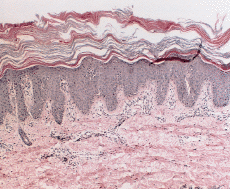

En enero de 2000, a los 17 años de edad, el paciente acudió de nuevo a la consulta presentando una generalización completa de sus lesiones hasta ocupar toda la superficie corporal. Este hecho había ocurrido de forma lenta y progresiva a lo largo de los últimos años. En la exploración, el paciente presentaba un aspecto eritrodérmico con descamación generalizada (Fig. 3), además de queratodermia palmoplantar con adelgazamiento de los dedos (Fig. 4) y ectropión. Se practicó una biospia cutánea que mostró una hiperqueratosis ortoqueratósica compacta con algunos focos de paraqueratosis y acantosis psoriasiforme con atrofia de la granulosa (Fig. 5). En la dermis se apreciaba una hiperplasia capilar superficial junto con un mínimo infiltrado linfohistiocitario perivascular. El paciente rehusó tratamiento con retinoides orales.

FIG. 5.--Biopsia cutánea tomada a los 17 años de edad. Existe hiperqueratosis ortoqueratósica compacta, atrofia de la granulosa con áreas de paraqueratosis, acantosis psoriasiforme e hiperplasia vascular dérmica superficial.